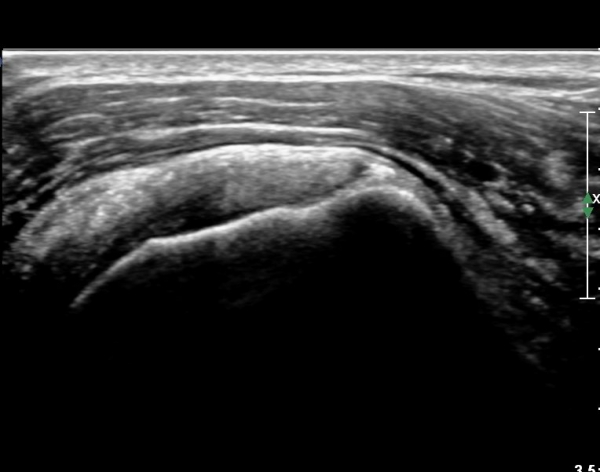

°ß°©ÇÏ±Ù°Ç ÇϺΠÁ¾´Ü¸é°Ë»ç¿Í Ⱦ´Ü¸é°Ë»ç °ß°©Çϱٰdz»  ¼®È¸È­ À½¿µÀÌ  °üÂûµÈ´Ù(»çÁø 3, 4).

°ß°©ÇÏ±Ù°Ç È¾´Ü¸é°Ë»ç»ó ¼Ò°áÀý ÇÊÁú°ñº¯È­¿Í °ß°©ÇÏ±Ù°Ç Áߺο¡ °í¿¡ÄÚ µ¢¾î¸®°¡ °üÂûµÇ°í

¼®È¸ À§ÂÊ(¸Ó¸®ÂÊ)ÀÇ ÈûÁÙÀÇ Àú¿¡ÄÚ º¯È­°¡ °üÂûµÈ´Ù(»çÁø 4, 5).